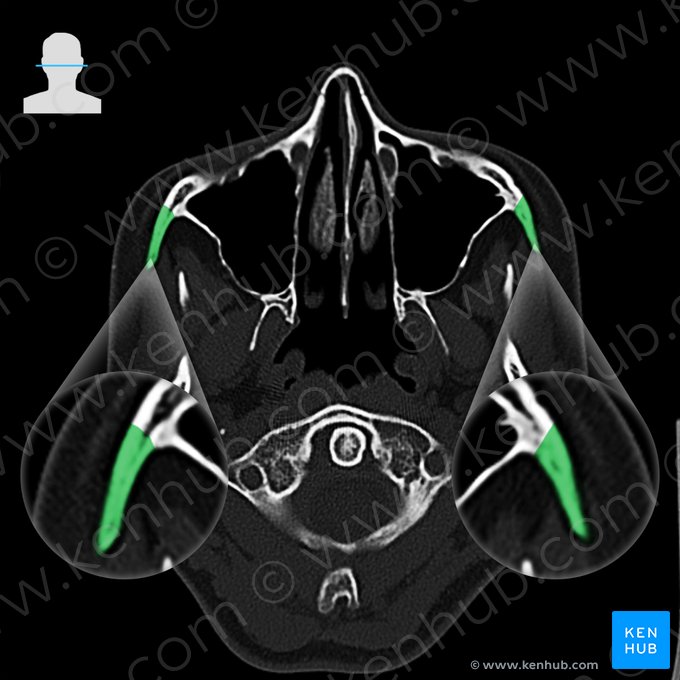

Bones of the head (CT)

Due to being highly saturated with calcium, the bones have the highest density on CT scans. Thus, they appear as white on scans. This enables us to evaluate the integrity of the bones, examine them for fractures, dislocations, osteolytic processes and dysplasia.

The following images will present you with the most important bony landmarks of the head and neck seen at the levels of jugular fossa, atlas (C1) and axis (C2).